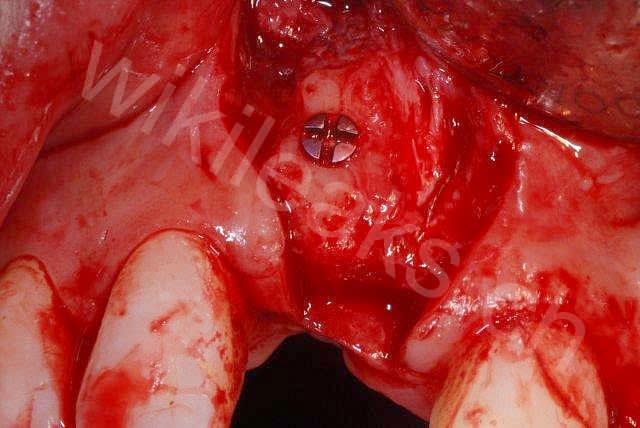

un cas que je ne retrouvais plus, et puis wikileaks l'a publié (les enfoirés c'était ultra-secret)

Planche1 mx3jxo - Eugenol

Planche2 xihoxk - Eugenol

15099scan eoou8g - Eugenol

2010 12 03 001 iltdrh - Eugenol